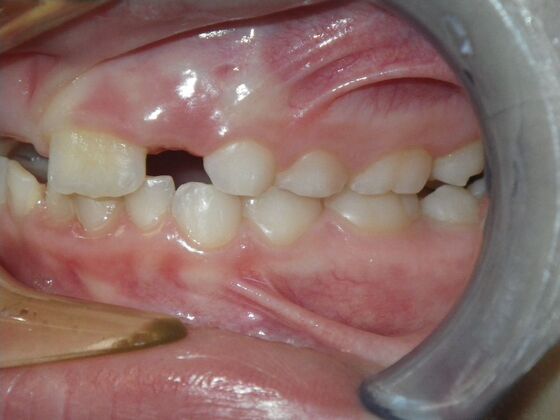

Patient presents with delayed eruption of the upper right central incisor and lower anterior crowding. Treatment plan to include exposure of right central incisor with bracket placement and correction of lower anterior crowding.